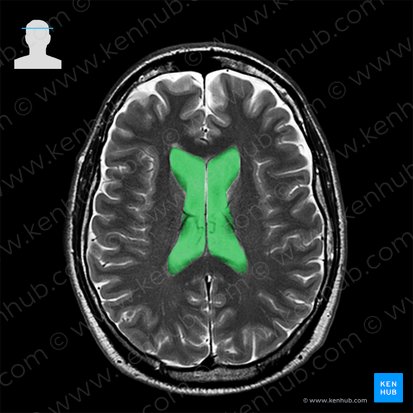

The lateral ventricles are the two irregularly shaped cavities located on either side of the midline of the brain. They are the most prominent structures on the majority of the axial brain scans. Like the entire ventricular system, they are seen as hyperintense structures on T2w as they contain a lot of fluid (cerebrospinal fluid).

Each lateral ventricle is a complex three-dimensional structure, consisting of a frontal horn, body, occipital and temporal horns.

The frontal horns are the largest components of the ventricular system of the brain. On MRI, they are seen as the two symmetrical laterally concave structures. Their anterior portions deviate laterally from the midline, being separated by the genu of corpus callosum. Posteriorly, they are closer to each other, being separated only by the septum pellucidum. The lateral surfaces of the frontal horn are directly related to the head and body of the caudate nucleus.

The body of the lateral ventricle curves around the superior aspects of the third ventricle and thalamus, being parallel to the midline and superomedial to the body of fornix. At the level of the splenium of corpus callosum, the body dives inferiorly and laterally, forming a triangular structure called the collateral trigone. The trigone is thus immediately lateral to the splenium of corpus callosum. It gives off a posterior, horizontal projection, called the occipital horn, as well as an anteroinferior projection called the temporal horn.